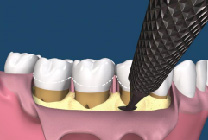

牙周再生手術是一種要求較高的牙周手術,其成功取決於多種條件的滿足,這些條件是:嚴格的適應證選擇;牙齦的炎症被有效控制;骨內袋中的肉芽組織應當儘可能被清除;生物膜在齦溝“領口”處應與牙根面盡量密合,以保證無齦上皮長入;生物膜與牙根之間應保持充分的空間,即足夠的膜根間隙;齦瓣應將生物膜完全覆蓋;術前術後有效的菌斑控制。(圖07-11)

圖11